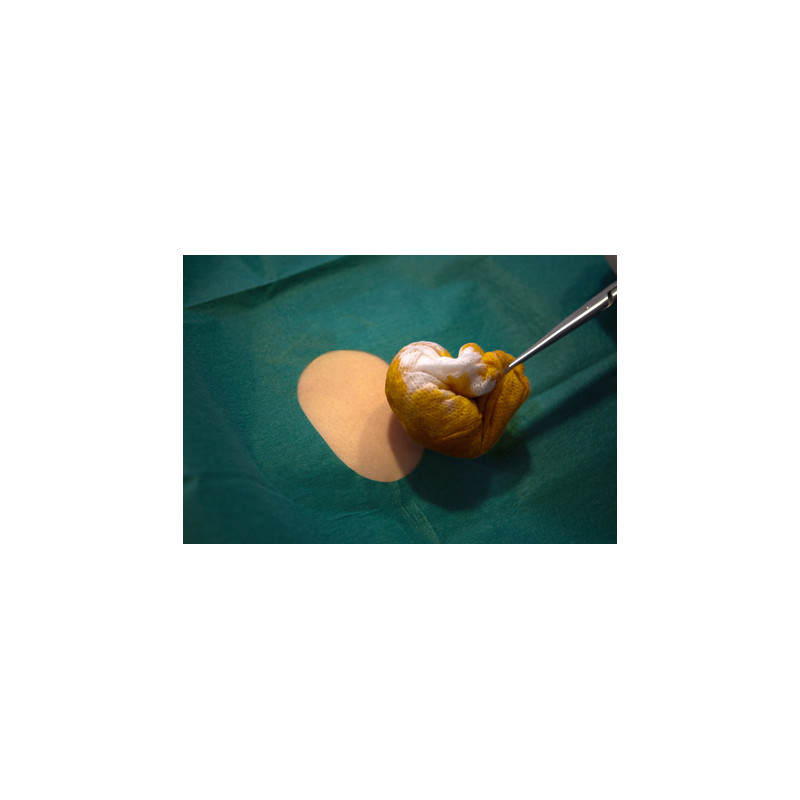

Das 2-lagige selbstklebende Lochtuch ist einzeln steril verpackt.

Es dient zur sterilen Abgrenzung des Operationsfeldes.

Die Außenlage nimmt Flüssigkeit auf.

Die Innenseite besteht aus einem sehr dichten, feuchtigkeitsundurchlässigen Material und bietet vollständigen Barriereschutz.